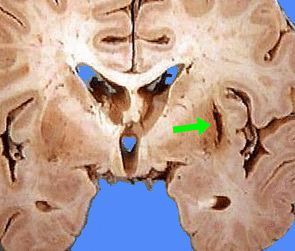

亚急性晚期

该期红细胞从血肿周边向中心逐渐开始溶解破裂 , 高铁血红蛋白分布于血肿液中 。 此时高铁血红蛋白仍然是那个和水亲密接触的顺磁性分子 , 没有一丝丝改变 , 所以对T1的影响不变 , 在T1像仍呈高信号 。 但是高铁血红蛋白从红细胞释放出来后 , 分布变得相对均匀 , 失去了磁场不均一性 , 因此局部磁敏感效应消失 , T2缩短效应消失 , 在T2像呈现原本水肿液的信号 , 即高信号 。

同时 , 在血肿周边巨噬细胞和胶质细胞的溶酶体也开始发挥作用 , 逐步吞噬血肿液的高铁血红蛋白 , 形成含铁血黄素 , 核磁信号表现为血肿周边的低信号环 , T2像最为明显 。 含铁血黄素具有明显的顺磁性 , 且位于巨噬细胞或胶质细胞内 , 构成磁场不均一 ,T2像呈低信号;另含铁血黄素为疏水性 , d>0.3纳米 , 不影响T1 , 无“造影剂增强”效应 。